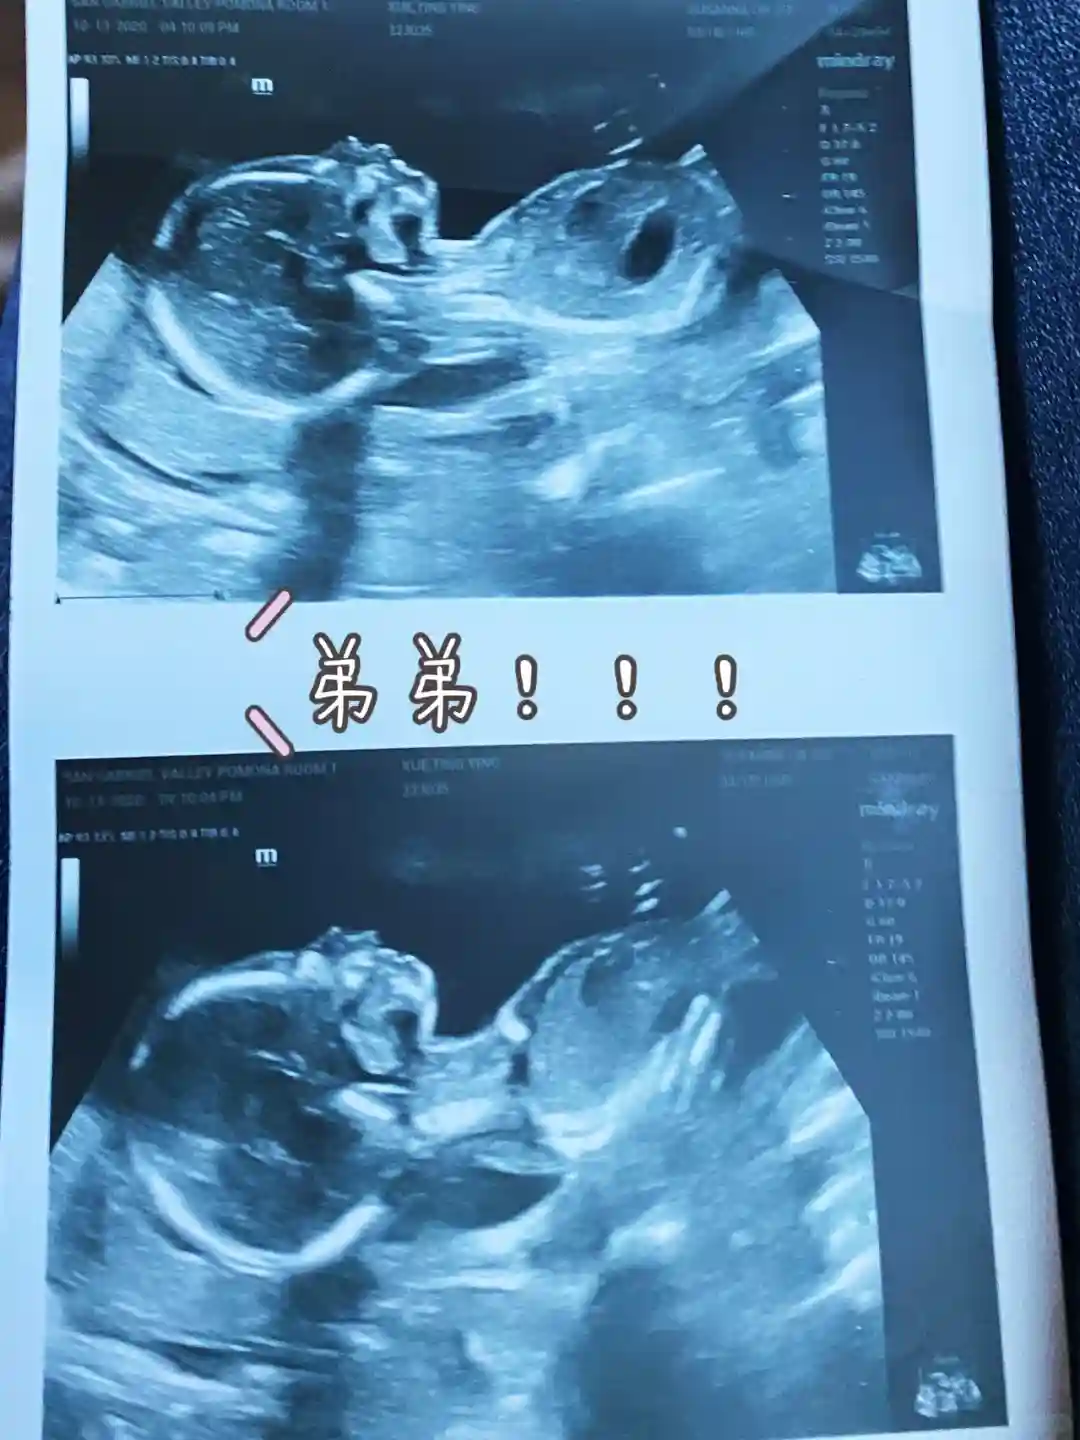

本来说好不要二胎的,结果今年6月份二宝突如其来(没有一点点防备也没有一丝顾虑你就这样出现...)大条妈妈再次上线,由于姨妈延后,于是我吃了大约一个礼拜的藏红花OMG想想也是后怕。惶恐之中买了验孕棒,又中啦,既来之则安之没什么好怕的,不舍得打掉这个小生命!但是这次真的是惨,前四个月也是累加嗜睡,但是这个程度基本就是在床上起不来那种,吃啥都没胃口,各种恶心呕吐,头痛,整个人水肿。以为反应那么大应该是个妹妹了,就这样浑浑噩噩过了差不多4个月(完全没法在意大斯丁BB了,觉得有点对不起他)验玩染色体医院电话打来:Boy! What?所以那些凭反应判断男女的都是谎话!而且二胎特别显怀,5个月的时候肚子就很明显了,而且已经开始耻骨痛。一胎要生的时候也就比现在大一点点而已。四个月的时候去了次黄石哈哈哈真的是不怕死的大条妈妈。现在24周多了,希望接下来一切安好,明年顺利让二宝落地!!!总之,生一胎玩儿似的,怀二胎玩儿命似的……不管怎样,孕妈们一定要保持轻松良好的心态呀!